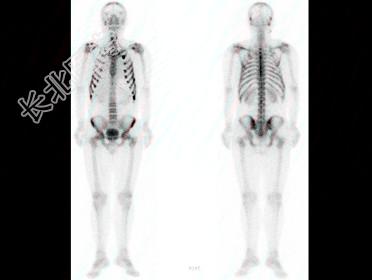

多项选择题男,36岁, 诉晨起酸痛数月,行Tc-MDP骨显像如图, 对此影像描述正确的是 ( )

A、是超级骨显像

B、颅骨散在圆点状浓聚提示病理过程的出现

C、提示肺性肥大性骨关节病

D、提示多发性骨髓瘤

E、提示多发骨转移